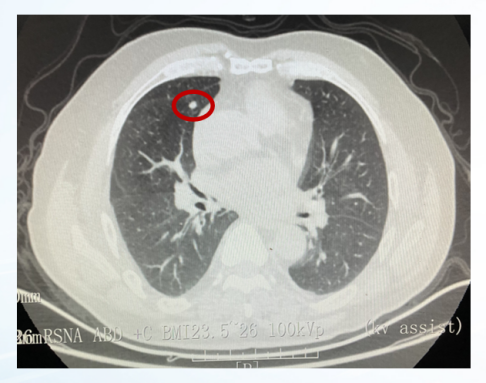

影像学评估:

图22、呋喹替尼治疗期间,患者肺部转移灶胸部增强CT评估情况:左(2020-10-23)、中(2021-05-27)、右(2021-07-06)